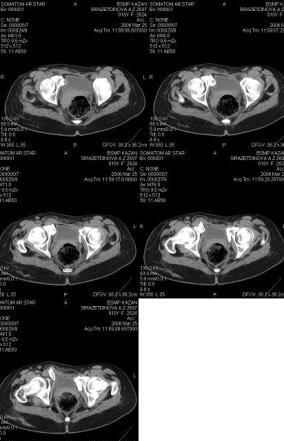

Re: Неправильно сросшийся перелом костей таза

Anton Kovalenko 10 Апрель 2006, 11:49

Предоставляю срезы. Если пациентку функционально ничего не беспокоит, стоит ли навязывать ей лечение.